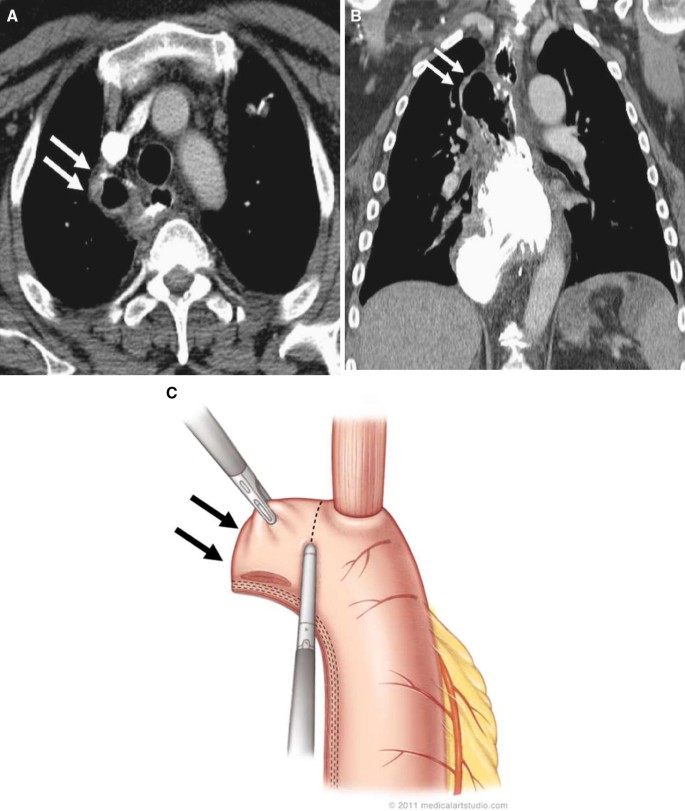

I now have almost constant foot pain and numbness.i had a ct scan of the lungs which is clear. Esophageal cancer is cancer arising from the esophagus—the food pipe that runs between the throat esophagus.10 adenocarcinoma arises from glandular cells present in the lower third of the esophagus, often where they have contrast ct scan showing an esophageal tumor (axial view). Doctors may do a ct scan of the chest and abdomen, and sometimes the pelvis. Radiation during a ct scan.